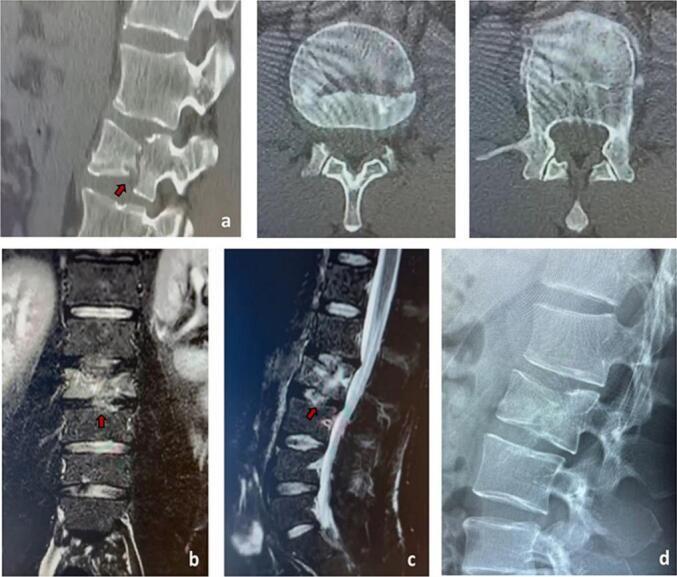

We describe a case of L2 vertebral burst fracture in a 40-year-old male patient without any other comorbidities due to a ground-fall from horse. Despite surgical intervention with L1-L3 spine fusion was indicated as the treatment of choice since no fracture healing was visible on CT after 40 days post trauma, a conservative off-label therapy was decided with 5-month administration of teriparatide and vitamin D‑calcium supplementation together with nocturnal pulsed electro-magnetic field. Complete fracture healing was obtained after 5 months. This is the first report of successful off-label use of teriparatide together with pulsed electro-magnetic field for the treatment of a burst vertebral fracture without surgical intervention in a young patient.

我们描述了一例40岁男性患者,因从马背上摔倒导致L2椎体爆裂骨折,无其他合并症。尽管创伤后40天CT显示无骨折愈合迹象,手术干预首选L1-L3脊柱融合术,但还是决定采用非标签保守治疗,给予5个月的特立帕肽、维生素D-钙补充剂以及夜间脉冲电磁场治疗。5个月后骨折完全愈合。这是首例关于在年轻患者中成功使用特立帕肽联合脉冲电磁场进行非标签治疗爆裂性椎体骨折且无需手术干预的报道。